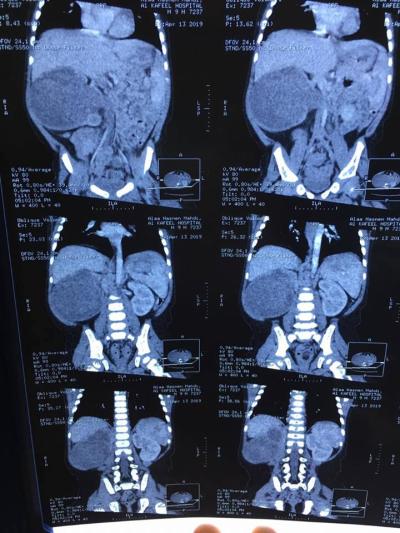

The head of the medical team, Dr. Sarmad al-Rubaie, a pediatric surgery specialist, said: "A quality surgical operation was conducted to a 9-month-old baby who was diagnosed with a tumor in the right kidney, with success"

Explaining: "The tumor is of the type (Wilms' tumor) that was attached to the main blood vessels in the abdomen and extends down and inside the right ureter."